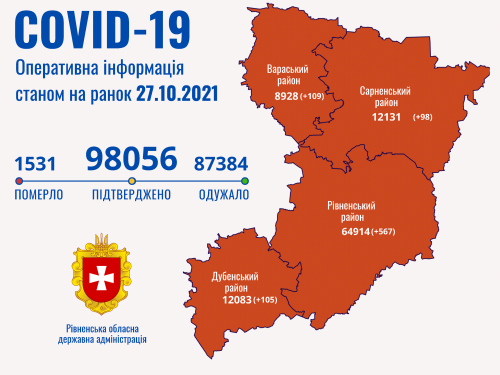

Пів тисячі - у важкому стані, 9 жителів Рівненщини померли за добу від коронавірусу